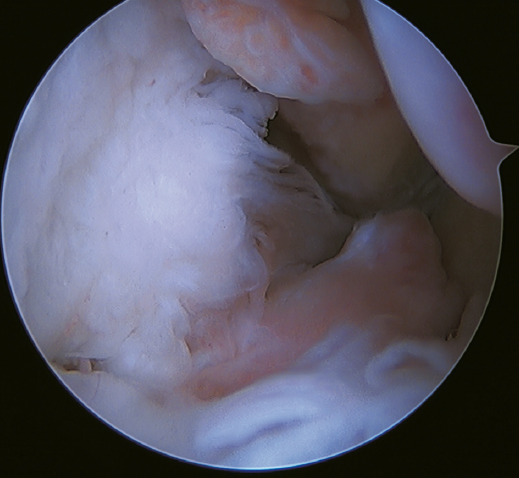

Un reciente consenso(64) recomienda la reconstrucción del LTFA y el LCF (Figuras 5 y 6) en aquellos casos de laxitud generalizada o cuando existe una mala calidad tisular. Otras indicaciones serían cuando existen dudas de la estabilidad subtalar o en aquellos pacientes con rotura del LCF. Para algunos autores, el IMC superior a 30 kg/m2 también sería una indicación para esta técnica.

Figura 6. Imagen artroscópica de una doble reconstrucción con aloinjerto del ligamento talofibular anterior (1) y del ligamento calcaneofibular (2), objetivándose la correcta tensión y posicionamiento de los fascículos.